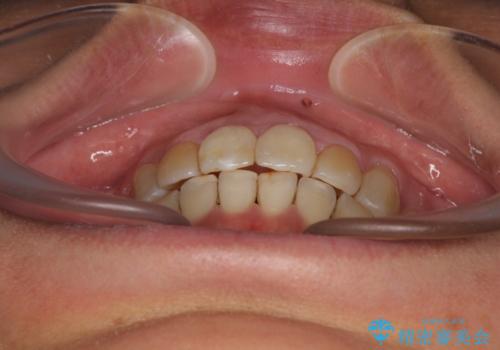

前歯の後戻り インビザラインでの再矯正治療

- かつて抜歯矯正を行ったものの、後戻りをしてしまったとのことで来院された患者様です。

上顎前歯が前突し、隣の歯が裏側に移動してきている状態でした。

舌のトレーニングをしっかりと行ってくださり、10ヶ月で希望通りの歯列となりました。

日頃から飲まれる飲み物の影響で着色しやすいため、来院の度に着色除去のクリーニングも行っていました。